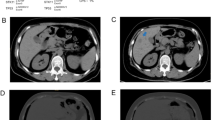

A Western blot analysis of MAPK signaling pathway in MDA-MB-231 and LM2. B IHC staining of p-ERK and p-JNK in primary tumors and lung metastases formed by MDA-MB-231 cells. C Western blot analysis of STC1 in LM2 treated with MAPK signaling pathway inhibitor (10 μM) for 24 h. D RT-qPCR was performed to detect the relative expression of STC1 mRNA in LM2 treated with JNK signaling pathway inhibitor SP600125 (10 μM). E Correlation analysis of STC1 and JUN mRNA expression in metastatic lesions of breast cancer patients (data from GSE14020). F Schematic diagram of STC1 promoter displaying locations of primer pairs, covering c-Jun binding sites, which were used for qPCR analysis following chromatin immunoprecipitation with an antibody against c-Jun (left). The qPCR analysis of STC1 promoter fragments pulled down by c-Jun and IgG antibodies in chromatin immunoprecipitation (right). The p values were obtained by unpaired t-test or one-way ANOVA test with Dunnett’s multiple comparisons test or Pearson correlation analysis. Scale bars, 100 μm. STC1 stanniocalcin 1, IHC immunohistochemistry, ChIP chromatin immunoprecipitation. ns no significance, p > 0.05; **p < 0.01; ***p < 0.001.

The lung is a relatively high-oxygen environment and faces more external stimuli [41]. To survive and develop continuously in the lungs, tumor cells must adapt to this environmental pressure. As is well known, the MAPK signaling pathway is susceptible to activation by extracellular stimuli [42]. We found that compared with MDA-MB-231 cells, the MAPK signaling pathway was activated in lung metastatic breast cancer LM2 cells, which manifested as increased phosphorylation of ERK and JNK protein (Fig. 7A). Immunostaining indicated that the levels of ERK and JNK phosphorylation in lung metastases formed by MDA-MB-231 cells were higher than those in carcinoma in situ formed by MDA-MB-231 cells (Fig. 7B). This demonstrated that the MAPK signaling pathway was activated in lung metastatic breast cancer cells. STC1 is known to be a cellular stress response factor [21]. Therefore, we next investigated whether the activated MAPK signaling pathway contributes to the expression of STC1. After treatment with MAPK signaling pathway inhibitors for 24 h in LM2 cells, it was found that the JNK inhibitor SP600125 could significantly downregulate the protein level of STC1 (Fig. 7C). Meanwhile, RT-qPCR results showed that the mRNA level of STC1 was significantly downregulated (Fig. 7D). This indicated that the transcription of STC1 mRNA could be regulated by the JNK signaling pathway. C-Jun is the most important transcription factor of the JNK signaling pathway. We found a correlation between the expressions of JUN mRNA and STC1 mRNA in the metastases of breast cancer patients, suggesting that there may be a regulatory relationship between c-Jun and STC1 (Fig. 7E). The binding site of the transcription factor c-Jun was predicted in the promoter region of STC1 by the JASPAR database. Chromatin immunoprecipitation–qPCR in LM2 cells indicated that the enrichment efficiency of the transcription factor c-Jun in the predicted binding site of STC1 promoter region was much higher than that of IgG control, indicating that the transcription factor c-Jun can directly bind to the promoter region of STC1 (Fig. 7F). These results revealed that the activated JNK signaling pathway in lung metastatic breast cancer promotes the STC1 expression.